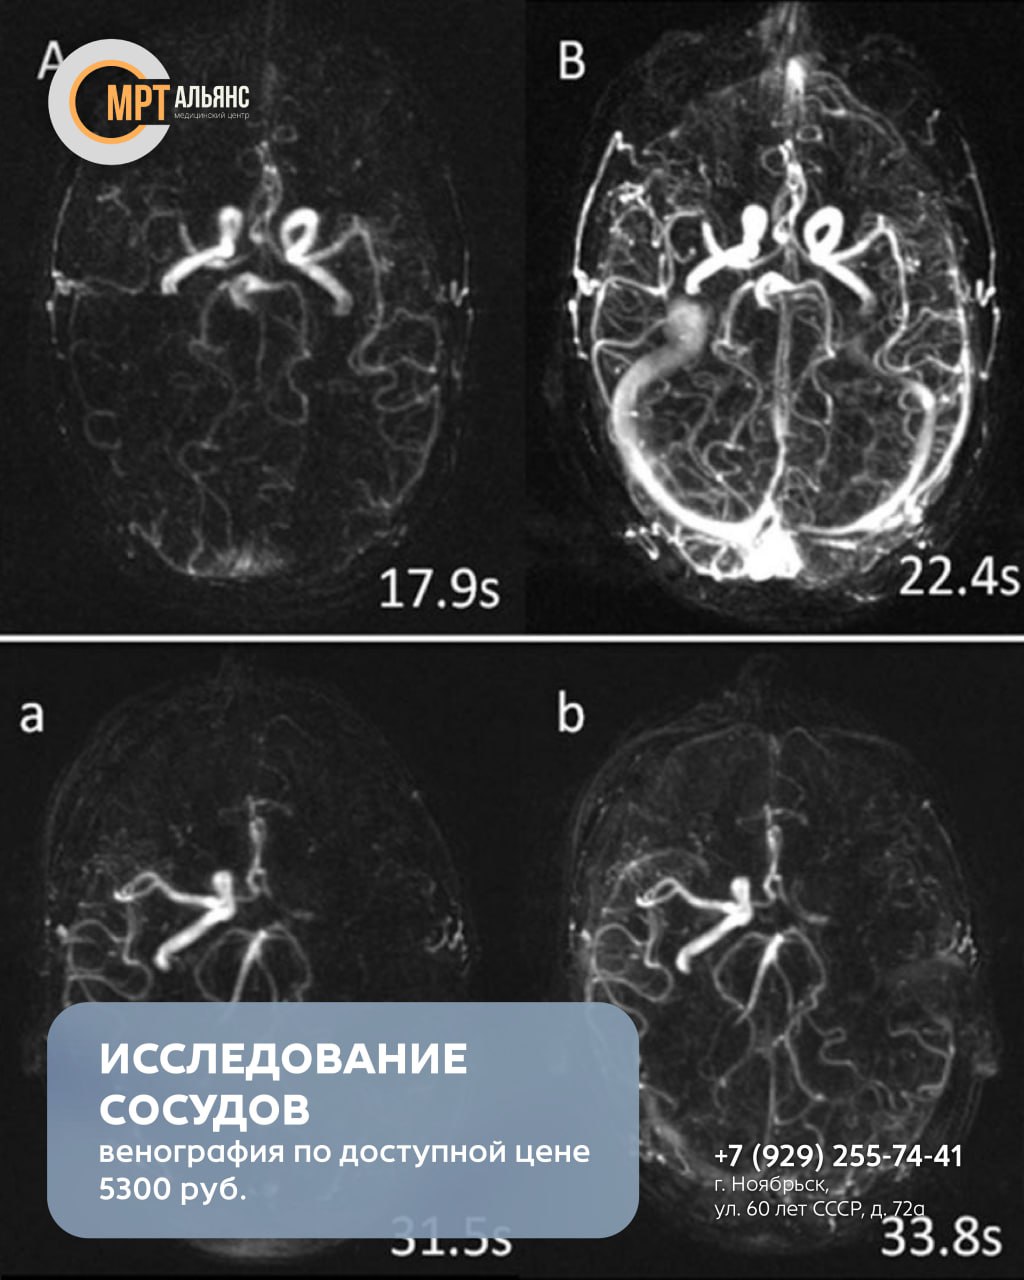

Позволяет выявить малейшие нарушения венозного кровотока и диагностировать:

· Тромбоз венозных синусов

· Аномалии развития сосудов

· Венозные мальформации

· Прорастание опухоли в сосуды

Показания к исследованию:

· Частые головные боли и головокружения без причины

· Посторонний шум в ушах

· Предобморочные состояния и обмороки

· Проблемы со сном, концентрацией и памятью

· Снижение остроты зрения

· Перенесенные травмы головы

Важно: перед исследованием сообщите врачу о наличии кардиостимулятора, металлических имплантов или клипс на сосудах